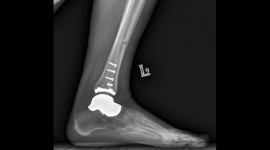

Jesienią odbyły się pierwsze w Polsce (i jedne z pierwszych w Europie) innowacyjne operacje stawu skokowego z wykorzystaniem hybrydowego wszczepu. Ich istotą było połączenie implantu kości skokowej z endoprotezą stawu skokowego. To rozwiązanie dla pacjentów z dużym uszkodzeniem kości skokowej.

Nowa proteza składa się z indywidualnie wykonanego, „szytego na miarę” implantu kości skokowej, który zastępuje blokującą ruch w stawie skokowym i podskokowym zniszczoną kość skokową, oraz połączonego z nim elementu piszczelowego protezy stawu skokowego. W takim zestawieniu obie protezy tworzą wszczep hybrydowy, pozwalający na przywrócenie prawidłowego ruchu w stawie.

Innowacyjną protezę wszczepiono w Carolina Medical Center u ponad 50-letnich pacjentek ze zmianami zwyrodnieniowymi stawu skokowego i zniszczoną pourazowo kością skokową.

Implant kości skokowej może być alternatywnym sposobem leczenia dla pacjentów, dla których dotychczas nie było rozwiązania innego niż usztywnienie stawu skokowego lub obuwie ortopedyczne. Pierwsze tego typu operacje przeprowadzane były w Japonii. W Polsce, w niewielkim odstępie czasu, operacjom poddały się dwie pacjentki. Każda z kobiet od ponad 3 lat cierpiała z powodu jałowej martwicy kości skokowej – ruch stawu skokowego był całkowicie zablokowany, pacjentki nie miały możliwości stanięcia na całej stopie. Obie pacjentki chodziły o kulach i codziennie przyjmowały leki przeciwbólowe.